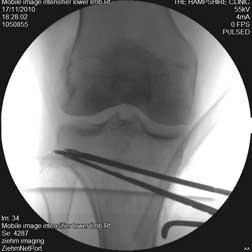

The image on the left is the fluoroscopic picture of the upper tibial region before the wedge was removed.